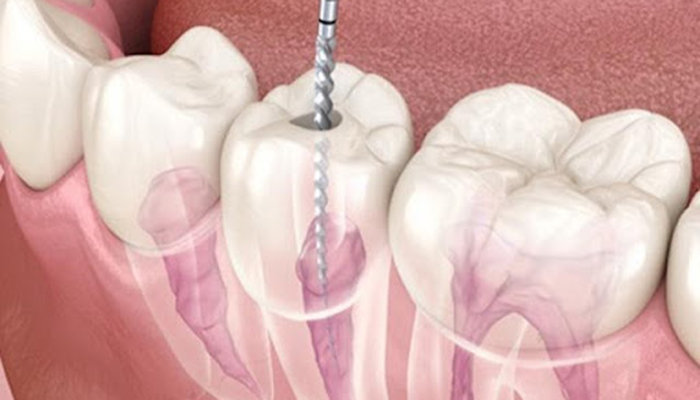

ニッケルチタンファイル

歯の神経の治療の際に、根の曲がりが強すぎると従来のステンレスの器具では根の先までのアクセスするために、歯の上部をより多く削らなければなりませんでした。

ニッケルチタンファイルを使用すると、根っこの形態が従来に比べてそのまま維持された状態で根の先にアクセスできるようになりました。

再治療の時など、根っこの形態が保存されているか否かで成功率に差が出てきます。

当院ではCTで根の状態を評価し必要に応じてニッケルチタンファイルを使用します。

ファイルの曲がり方の違い